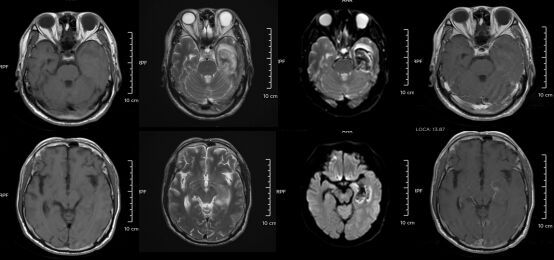

脑部磁共振报告显示其“双侧额颞部脑膜稍增厚伴强化”,提示脑膜炎。经5天抗病毒治疗,小李病情好转出院。